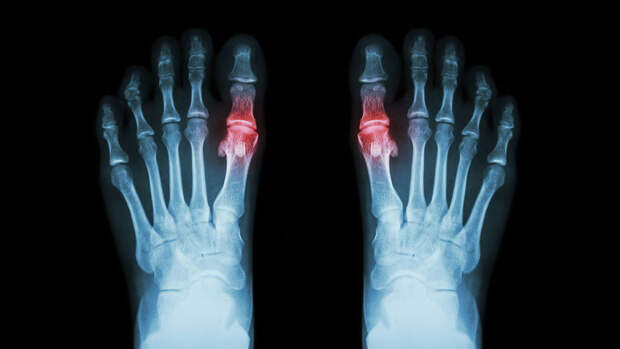

Кровопускание может быть эффективным методом борьбы с симптомами подагры, считают китайские ученые из Сычуаньской больницы интегративной медицины. Свои выводы они изложили в статье в журнале Complementary Therapies in Clinical Practice.

Объем крови варьировался от пары мл до более чем 10 мл. По оценкам исследователей, кровопускание вызывало на 36% меньше побочных эффектов, чем обезболивающие препараты, и было на 37% эффективнее по сравнению с ними в борьбе с болью. Кровопускание снижало уровень мочевой кислоты так же эффективно, как и обычные лекарства, но в большей по сравнению с ними степени снижало уровень С-реактивного белка, который при подагре связывается с кристаллами мочевой кислоты и вызывает воспаление.Хотя ученые настаивают на высокой эффективности кровопускания для борьбы с подагрой, рассмотренные ими работы были довольно низкого качества и имели много методологических недостатков. Полученные результаты не позволяют рассматривать кровопускание как равноценную альтернативу существующему лечению, но, возможно, дальнейшее изучение метода позволит получить более точные данные.